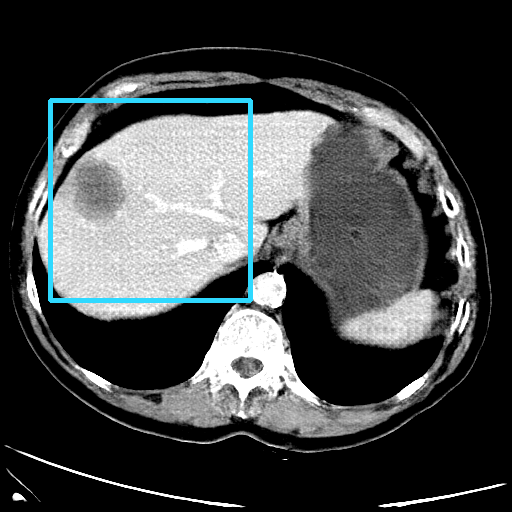

Refer to caption

(a) CT images.

(b) MRI images.

Figure 6: Lossy compression based attack on CT images (a) and MRI images (b) with a specific channel numbers (C8050\mathrm{C^{50}_{80}}) for the EP and IT Scenarios. StolenEPD1\mathrm{Stolen}^{\mathrm{D1}}_{\mathrm{EP}} denotes the decompressed images in the EP Scenario with a reduced D1 decoder.

Compression-Fidelity Compromise. Based on the previous results, we have selected the decoder D1D1 and the configuration of the latent and hyperlatent variables C8050\mathrm{C^{50}_{80}}, as the optimal architecture of the HiFiC encoder-decoder pair. In Fig. 6, we display more specifically the compression and reconstruction quality performances. In terms of reconstruction quality, we obtain a PSNR of approximately 40 for CT images and around 38 for MRI images while the MS_SSIM values are close to 1. This indicates an excellent perceptual quality of the reconstructed images that are hardly discernible from the original ones. In terms of compression efficiency, the Pratio\mathrm{P}_{\mathrm{ratio}} for CT images is approximately 0.015, indicating that the lossy image compression-based attack generated compressed images are 67 times smaller than those produced by the lossless zipped image compression-based attack. For MRI images, the Pratio\mathrm{P}_{\mathrm{ratio}} is around 0.12, 10 times higher than that of CT images, which can be attributed to the presence of a large uniform background in the skull-stripped original MR images.